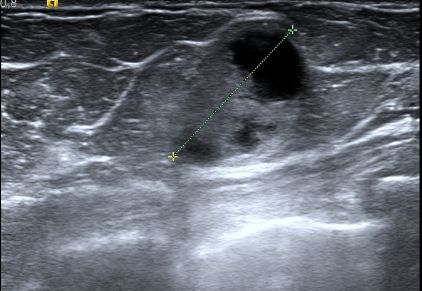

Das Ultraschallbild zeigt in der Zyste solide Anteile.![]() |

Histologisch 16mm großes papilläres DCIS.![]() | ||